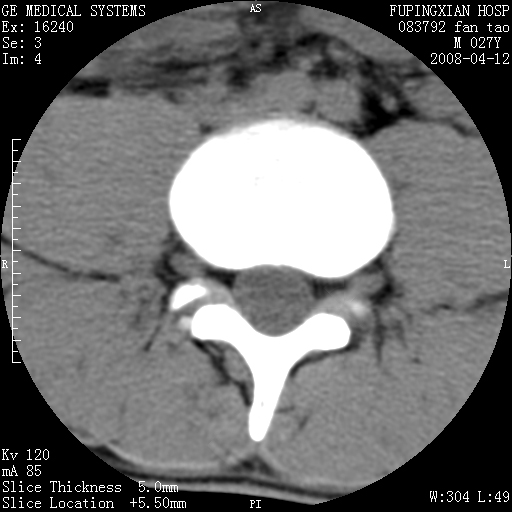

以下是引用前行在2008-4-13 13:53:00的发言:[br]椎间盘髓核终板下突出形成许莫氏结节及椎间盘突出,建议mr检查

以下是引用xclzq_910在2008-4-13 12:43:00的发言:[br]这个应该没什么了,椎间盘突出后反应性骨质吸收硬化.建议mr